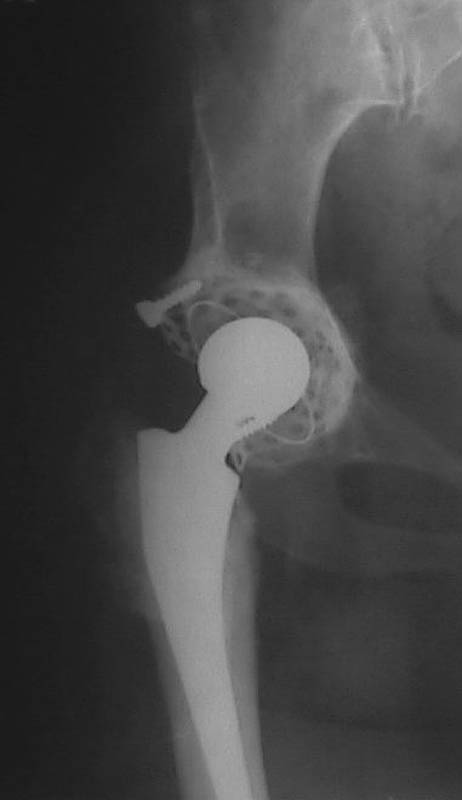

Вывих чашки

Мужчина, 38 лет. Двусторонний диспластический коксартрз, кифосколиоз. Правый сустав прооперирован 12.12.00, левый - в апреле 2003 г. Справа вывихнулась <чашка>.

Предполагается заменить <чашку>, наростив крышу <тутопластом>? Возможно ли использовать бесцементную <чашку>? Мнения? Заранее благодарю! С уважением, А.В.Владзимирский